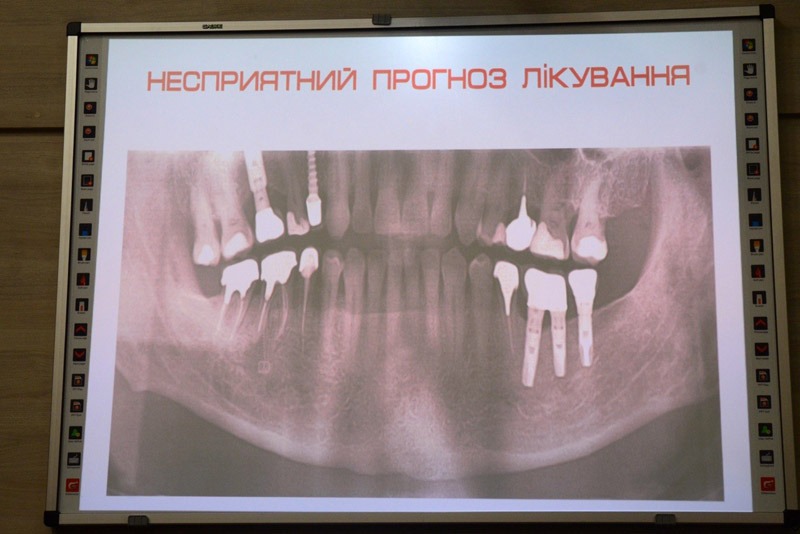

Під час лекції учасники розглянули практичні аспекти збереження кісткової тканини, алгоритми підбору імплантатів для різних клінічних випадків, а також типові помилки, які можуть вплинути на довгостроковий результат лікування.